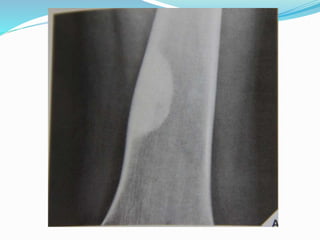

 subperiosteal resorpation

Mainly Radial aspect of the middle

Phalanx

 Soft tissue calcification

 subperiosteal

resorpation

Mainly Radial aspect of the

middle Phalanx

 Tunneling of cortices